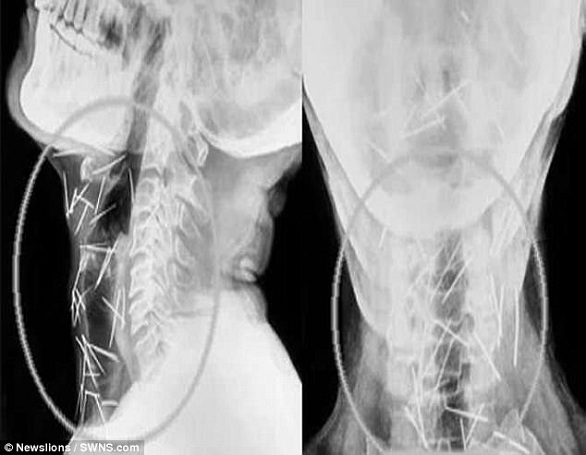

واضطر باديرلال مينا (56 عاماً) لزيارة 6 مستشفيات والخضوع لثلاث عمليات جراحية، لإزالة الدبابيس من ذراعيه وقدميه وعنقه، وحتى الآن تمت إزالة 91 دبوساً، البعض منها كان صدئاً للغاية، بعد أن تركت داخل جسده منذ عدة أشهر، بحسب صحيفة ديلي ميل البريطانية.

ويصر مينا وهو من كوتا شمالي الهند، أنه لم يغرس أياً من هذه الدبابيس داخل جسده، ولا يعرف كيف وصلت إليه، في حين يقول الدكتور لاليت موهان بارشار إن عدم إصابة مينا بأية أضرار دائمة أشبه بالمعجزة.

وأضاف الدكتور بارشار الذي أجرى العمليات الجراحية للمريض "شكل إخراج الدبابيس من جسمه بأمان تحدياً كبيراً بالنسبة لنا، خاصة وأن بعضها كان مغروساً في الرغامى والمري، وحتى في الشريان السباتي الذي يحمل الأوكسجين إلى الدماغ".

وكان مينا راجع المستشفى للمرة الأولى، وهو يشكو من آلام في القدم اليسرى، ووجد الأطباء نحو 75 دبوساً مغروسة في مناطق متفرقة من جسده، وفقد نحو 30 كيلوغراماً من وزنه، أثناء محاولته العثور على جراح على استعداد للمخاطرة بإزالة هذه الدبابيس.

وفي نهاية المطاف، قبل المعهد الآسيوي للعلوم الطبية التعامل مع الحالة، وعلى مدى 3 عمليات جراحية، تمت إزالة أكثر من 90 دبوساً من جسد مينا، ويقول الأطباء إنه بصحة جيدة، ولا يزال يتعافى من آثار العمليات الجراحية المعقدة.